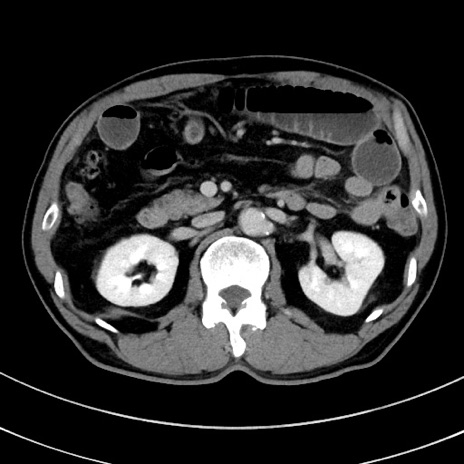

症例8(横断像)

【症例】 60歳代男性

【主訴】 黒色吐物

【現病歴】 4日前から嘔気自覚、2日前の朝食後にも嘔気あり、自分で手で嘔吐反射起こし嘔吐したところ血が混ざっていたため受診。

【既往歴】 5年前汎発性腹膜炎を伴う急性虫垂炎で手術、高血圧、前立腺肥大症、高脂血症

【身体所見】 腹部正中に手術癩痕あり 腹部平坦・軟圧痛なし膨満感あり

【データ】WBC 8400、CRP 4.54